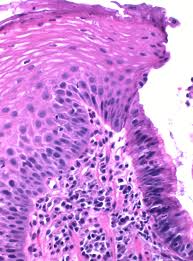

가슴 한가운데가 타는 듯 아프거나, 묵직하게 눌리는 느낌이 들면 가장 먼저 심장을 떠올리게 됩니다. 하지만 검사에서는 이상이 없다고 하고, 통증은 식사 후나 누웠을 때 더 심해진다면 역류성 식도염으로 인한 가슴 통증일 가능성을 생각해볼 수 있습니다. 역류성 식도염은 위산이나 위 내용물이 식도로 역류하면서 식도 점막을 자극해 염증과 통증을 만드는 질환입니다. 이때 나타나는 가슴 통증은 심장 통증과 매우 비슷해 혼란을 주지만, 양상과 상황을 잘 살펴보면 차이를 느낄 수 있습니다.

심장 문제로 인한 통증은 운동 중이나 긴장 상황에서 발생하고, 턱·팔·등으로 퍼지는 경우가 많습니다. 반면 역류성 식도염은 식사·자세·위산 자극과 밀접합니다.